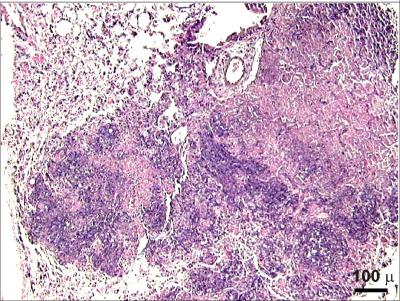

The study showed that CO triggers Mycobacterium tuberculosis ( Mtb ), the causative agent of tuberculosis, to shift from active infection to a drug-resistant dormant state. This is called latency, a global problem that results in tuberculosis escaping detection and treatment, and which contributes to overall tuberculosis transmission.

In the study, the researchers worked with Mtb cells under biosafe laboratory conditions and found Mtb proteins ‘sense’ CO at the molecular level, much like the bacteria’s proteins sense other gases in the lungs. The CO interaction is what led to a series of biological steps that sent Mtb into latency.